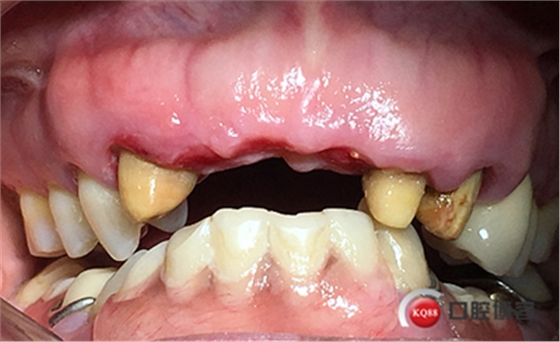

患者女性,52歲,缺失三顆牙,骨性前突,頜弓窄,身高175,魁梧,放了三顆牙是不是有點(diǎn)細(xì)?左上3開(kāi)膠了,牙體有腐蝕。

鄰牙重新備牙,制作臨時(shí)樹(shù)脂橋體,缺牙區(qū)三顆變?yōu)閮深w。下圖是術(shù)后一個(gè)月口內(nèi)照。